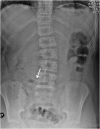

Emergency and trauma care produces a "perfect storm" for radiological errors: uncooperative patients, inadequate histories, time-critical decisions, concurrent tasks and often junior personnel working after hours in busy emergency departments. The main cause of diagnostic errors in the emergency department is the failure to correctly interpret radiographs, and the majority of diagnoses missed on radiographs are fractures. Missed diagnoses potentially have important consequences for patients, clinicians and radiologists. Radiologists play a pivotal role in the diagnostic assessment of polytrauma patients and of patients with non-traumatic craniothoracoabdominal emergencies, and key elements to reduce errors in the emergency setting are knowledge, experience and the correct application of imaging protocols. This article aims to highlight the definition and classification of errors in radiology, the causes of errors in emergency radiology and the spectrum of diagnostic errors in radiography, ultrasonography and CT in the emergency setting.